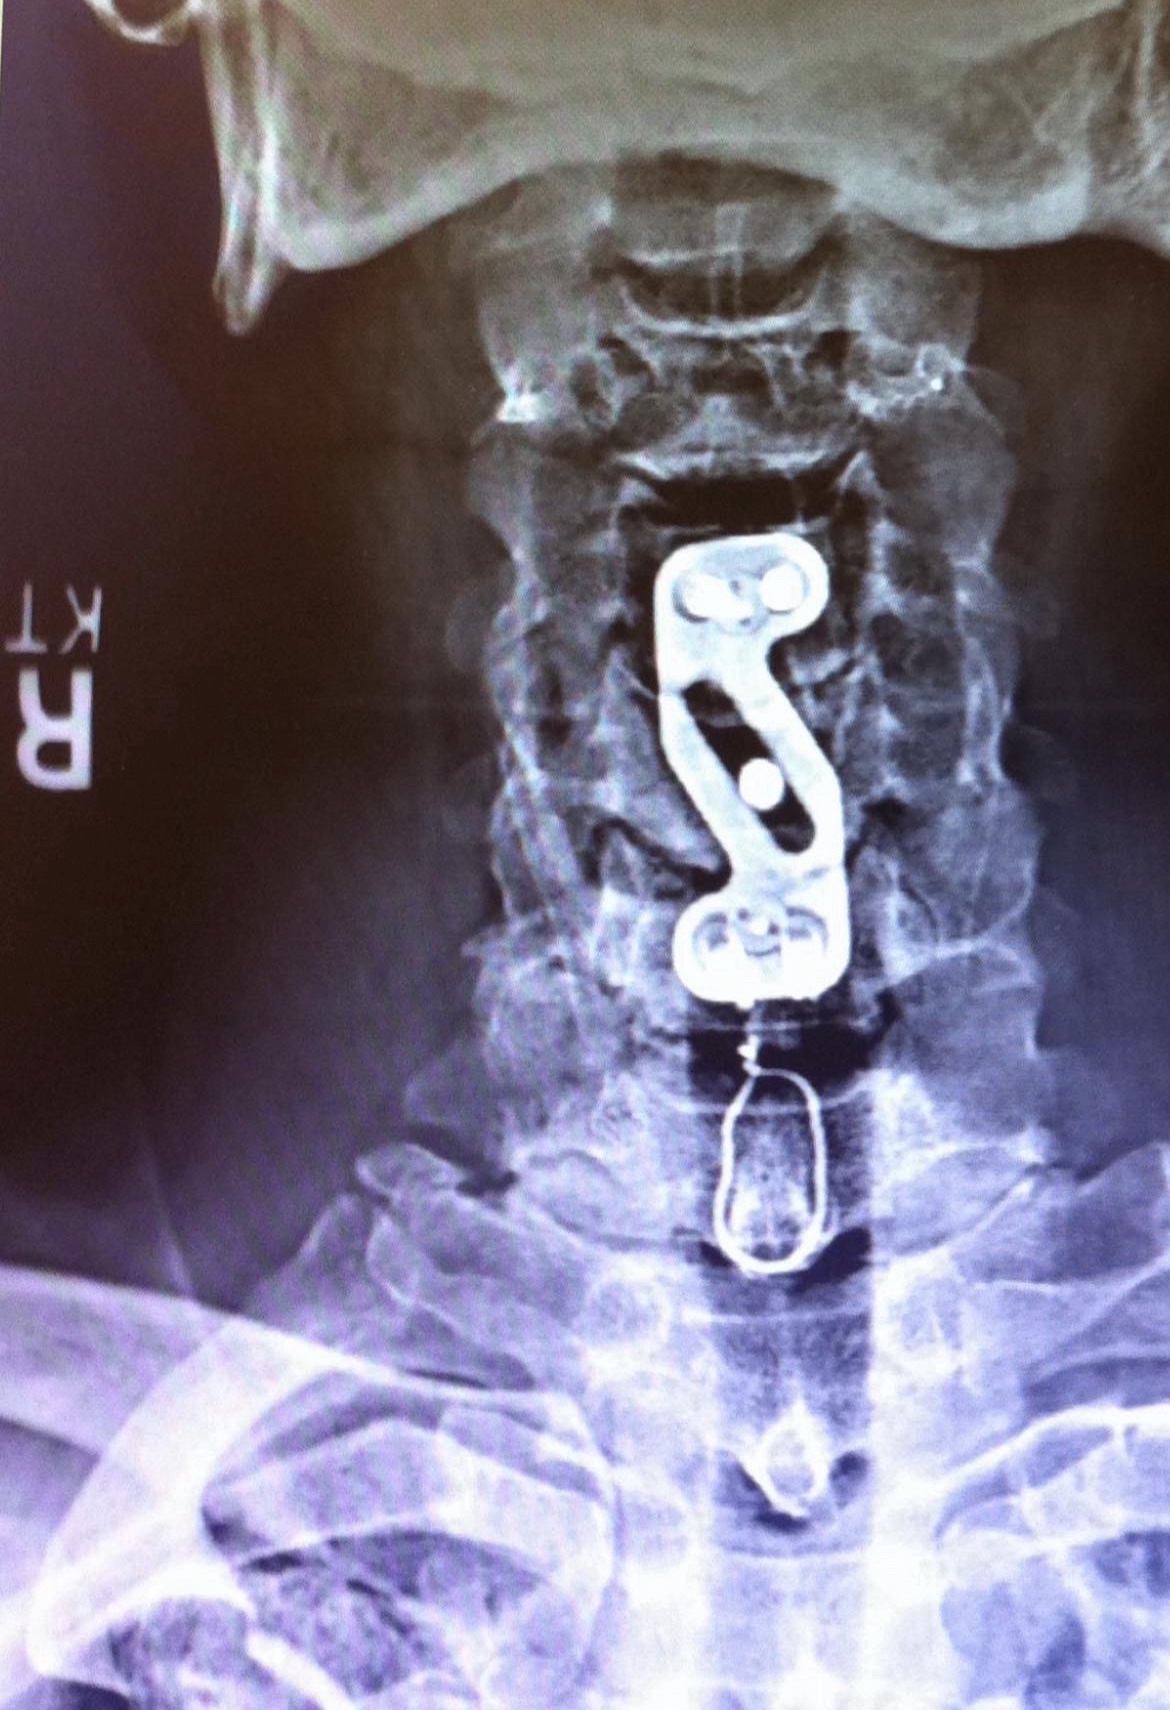

Back in 2005 when I was about to go crazy, this spine surgeon went in a put a metal plate, that extends across three discs and attached them with screws. Those show up in the photo below.

That fix took care of everything for 5 years but the stresses from the vertebrae being fused above caused the next disc to go. I was told at the time of the first fusing, that would possibly happen. Another trip to surgery in 2010 got my wire up job done. I call it that because it looks like a piece of baling wire went down around a piece of bone that sticks out and a with a twist up at the top, somehow fastened it around the plate or screw. That shows up in the same photo up above.

But what freaks me out about the side view photograph, it appears that the wire is hanging out in air, or in this case meaty flesh, because there is no bone showing up, nor is it attached to the metal pieces, as you can see in the photo below.

Like I said in the beginning I’m no doctor, but seriously this looks and feels like I got a piece of wire jabbing me in the neck. Isn’t that a piece of wire floating around with a sharp barb on the end? It sure feels like it.